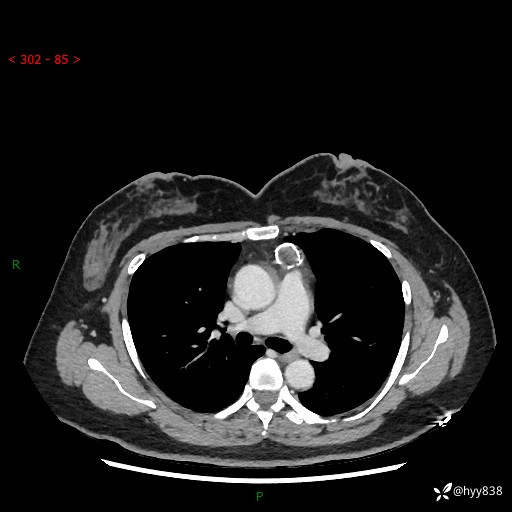

中年女性,检查发现纵隔占位3月余。圆圆的肿物,周围环绕一圈钙化---结果公布~

现病史:患者于3月前体检行胸部CT检查发现纵隔占位,患者平素无明显咳嗽咳痰,无心慌、胸闷、胸痛、呼吸困难、低热、盗汗,无头痛、头晕,无腹痛、腹胀等不适。现患者欲求进一步治疗,遂来我院就诊,以“纵隔占位”收入我科。 患者自起病以来,精神可,睡眠可,饮食可,大小便正常,体重无明显改变。

胸部CT平扫+增强